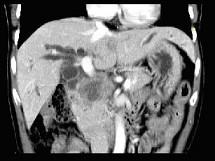

问题 患者,男,51岁,右上腹隐痛两月余,CT扫描如图,最可能的诊断是()

选项 A.胆囊癌伴肝门胰头周围转移 B.胆囊息肉 C.胆囊黄色肉芽肿 D.慢性胰腺炎并胆囊息肉 E.胆囊腺瘤及慢性胰腺炎

答案 A